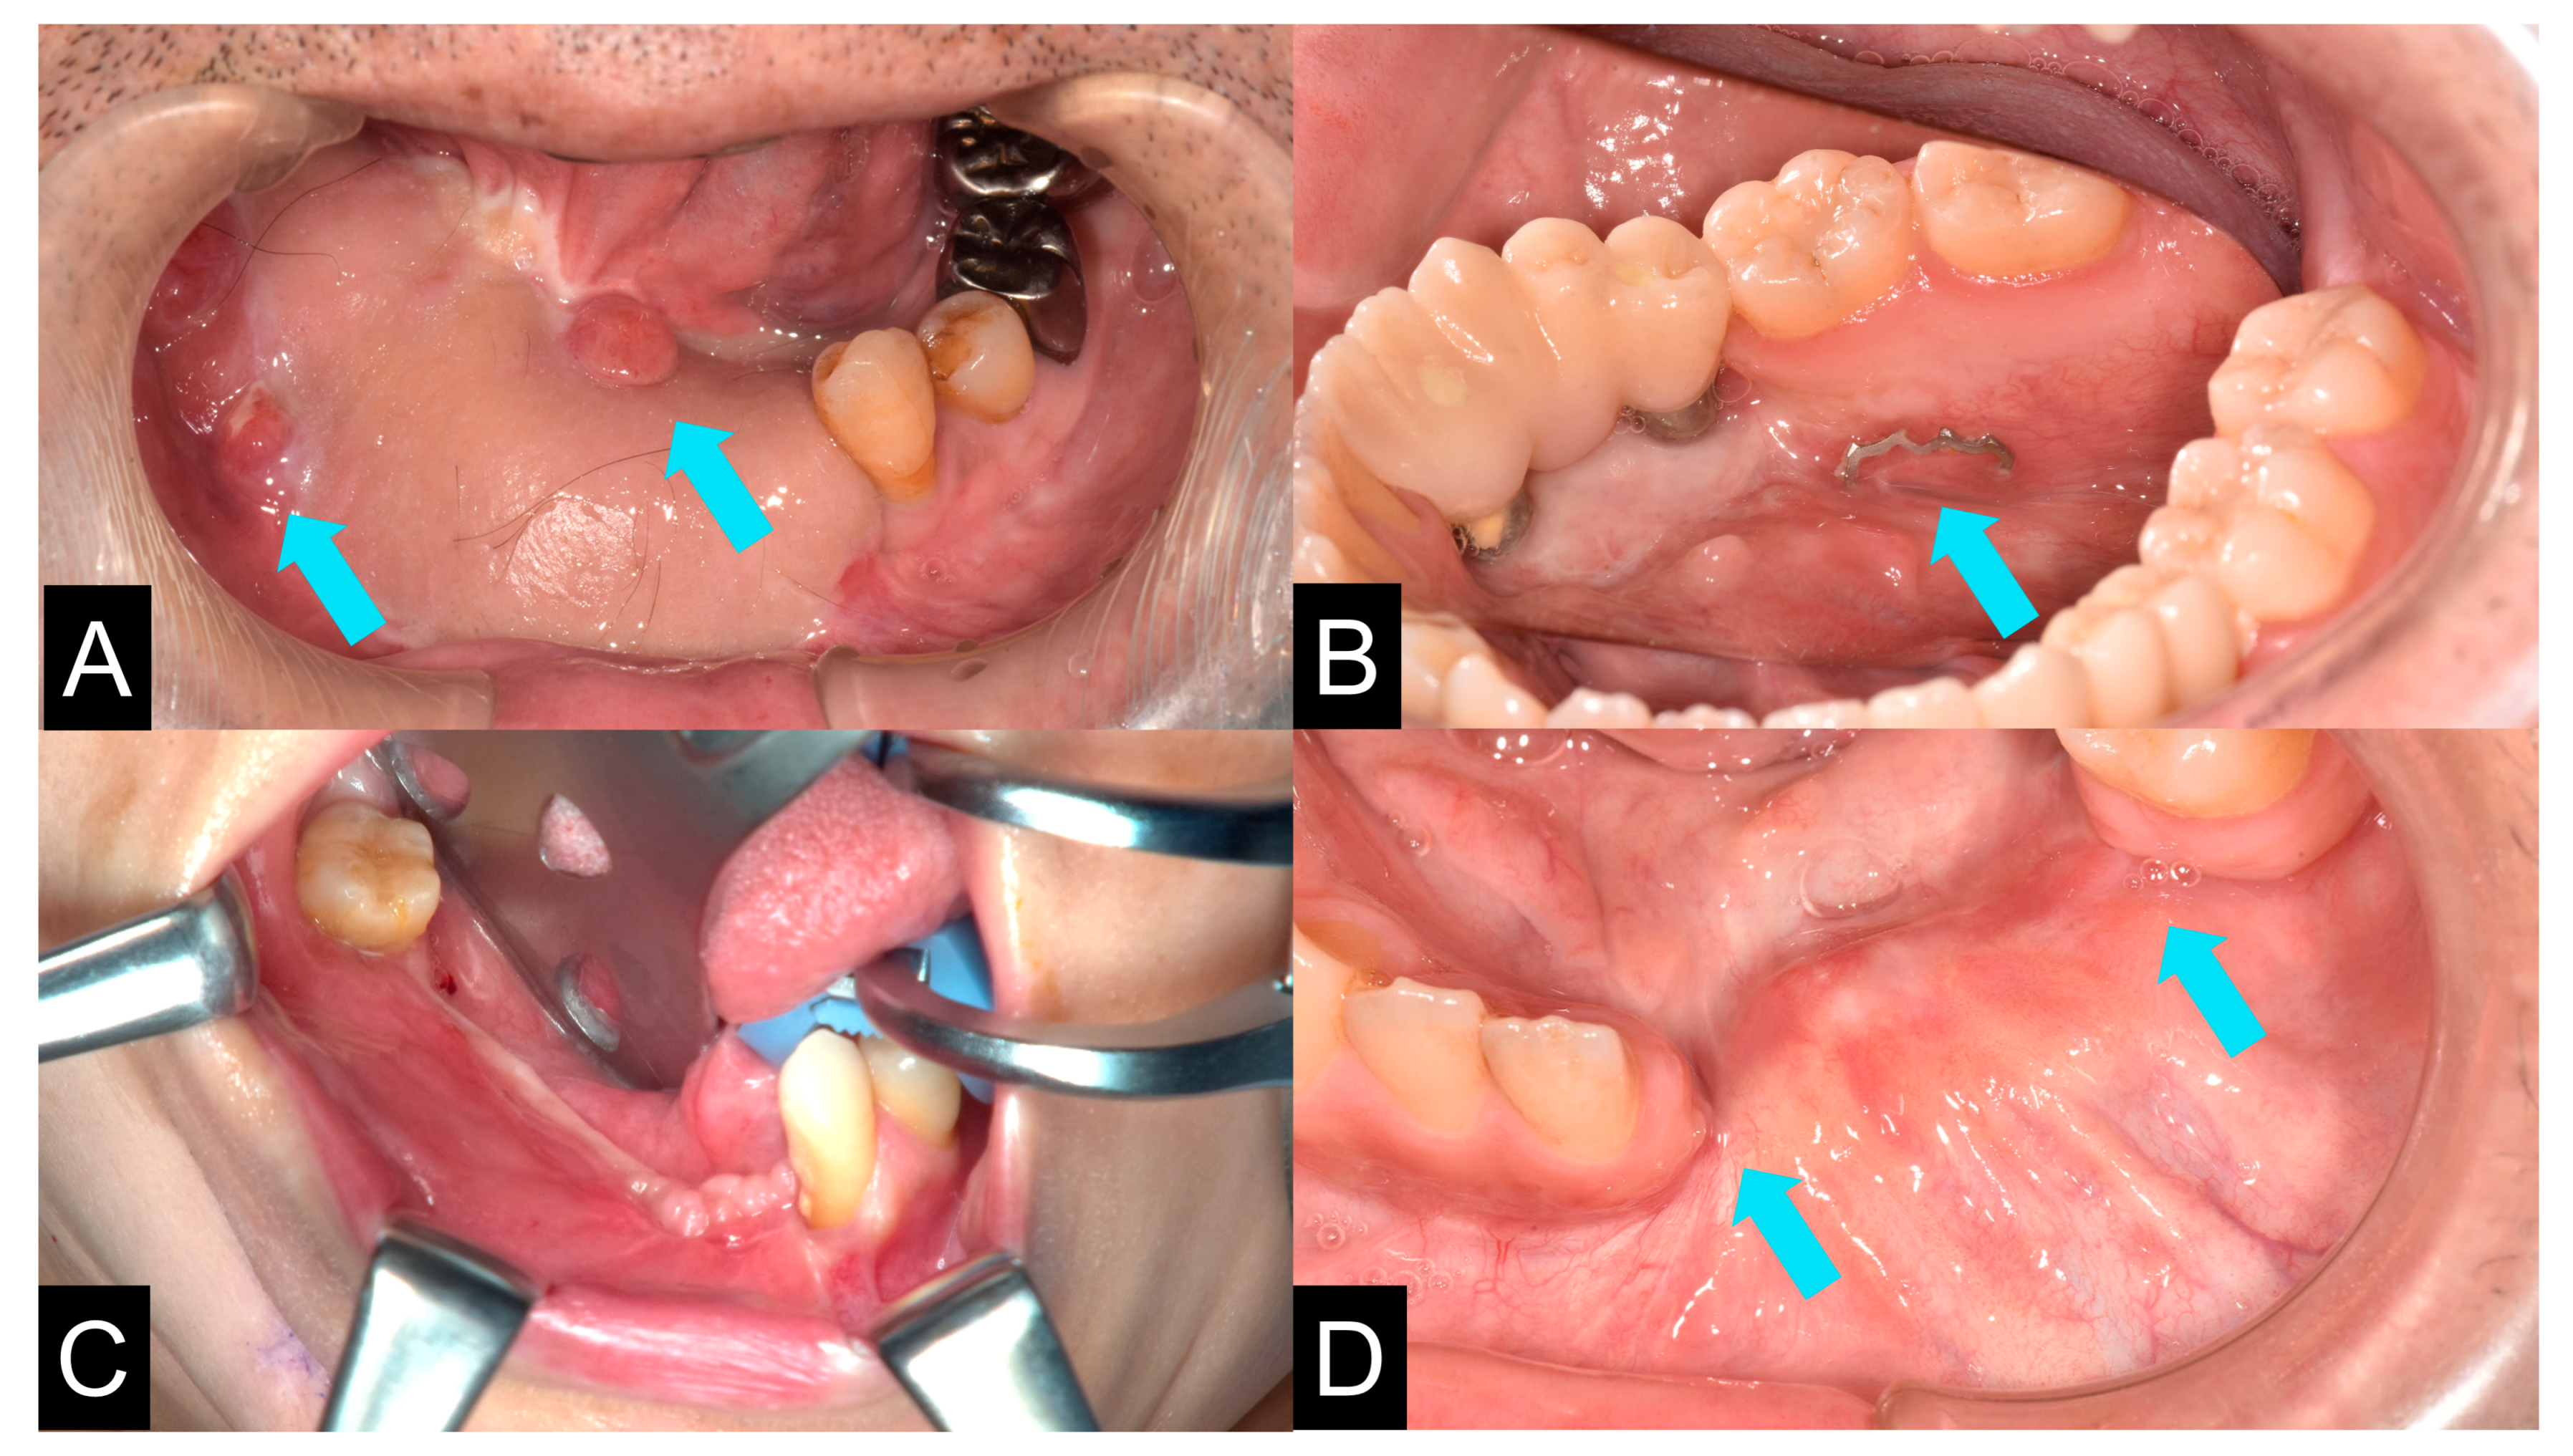

2.8. Clinical Procedures

3.3. Evaluation of Reconstructed Mandible